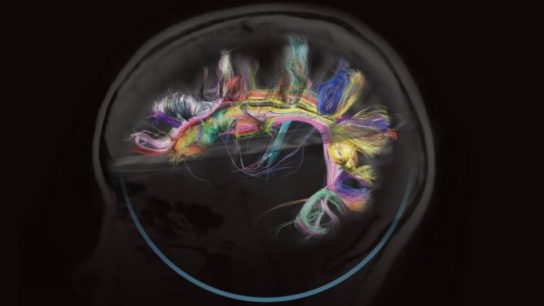

Adopting a more open-access environment crucial to developing new technologies for understanding the human brain.

Cerebrospinal fluid, neuroimaging techniques, and blood and skin peripheral tissues may hold the answers to recognizing Alzheimer’s disease earlier.